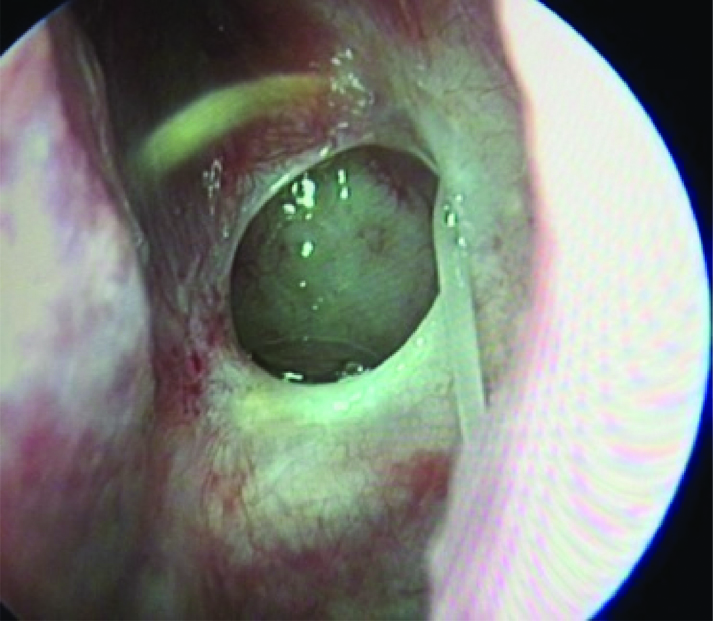

ВВЕДЕНИЕ В настоящее время в связи с распространением лучевых (МРТ, КТ) и визуальных (эндоскопия) методов диагностики наблюдается увеличение количества случаев изолированного сфеноидита [1, 2, 3]. Удельный вес изолированного сфеноидита в общей структуре заболеваний околоносовых пазух (ОНП), по данным литературы, составляет не более 5% [4, 5, 6]. Однако абсолютные цифры с учетом огромного количества случаев воспалительной патологии ОНП могут быть весьма значительными. В структуре синуситов все больше резистентных (устойчивых к лечению) форм, в том числе грибковых [7]. Данные о распространенности патологии весьма скудные, в структуре статистической отчетности стационаров и поликлиник сфеноидит как самостоятельная нозологическая форма отражается крайне редко. В то же время относительно невысокая распространенность нередко обусловливает пассивную позицию специалистов при дифференциальной диагностике поражений клиновидной пазухи (КП). Основное место в дифференциальной диагностике у данной группы пациентов занимают компьютерная томография (КТ) и магнитно-резонансная томография (МРТ). Однако трактовка результатов исследований не всегда однозначна и может приводить как к гипердиагностике, так и, наоборот, к гиподиагностике сфеноидита, выражающейся в недооценке данных лучевой диагностики и обьективной картины и нередко приводящей к развитию хронических и осложненных форм. Пациенты направляются к лор-врачу только после длительного, безуспешного лечения у специалистов смежных специальностей, что влечет высокий уровень гиподиагностики сфеноидита и наличие осложненных форм [8]. Дифференциальная диагностика патологического процесса в пазухе на дооперационном этапе чрезвычайно важна, поскольку необдуманное вмешательство может вызвать тяжелые и даже фатальные осложнения [9, 10]. От 5% до 30% всех изолированных поражений клиновидной пазухи составляют пациенты с неинвазивной грибковой формой [11, 12]. Для хронического сфеноидита характерно латентное (скрытое) течение, которое не всегда диагностируется на ранних стадиях [13, 14]. По данным ряда исследователей, частота патологических находок в клиновидной пазухе при аутопсии лиц, прижизненный диагноз «сфеноидит» у которых не был установлен, составляет от 10% до 68% [15, 16]. Очень важно изучение вопросов ремоделирования в клиновидной пазухе, в том числе явлений остеита при грибковых формах [17]. Осложненное течение изолированного сфеноиди-та - нередкое явление, при этом основным фактором развития осложнений является несвоевременная диагностика. Наиболее часто встречаются осложнения, связанные с вовлечением в патологический процесс глазодвигательных нервов, в особенности VI пары - n. abducens [4, 9, 16]. В литературе можно встретить наблюдения инвазивных, генерализованных форм грибкового сфеноидита с быстрым развитием офтальмологических, интракраниальных и системных (септических) осложнений [7, 12, 14]. Тактика лечения при изолированных поражениях клиновидной пазухи, по данным литературы, различная. Часть авторов считает наличие изолированного сфеноидита, особенно грибковых форм, мукоцеле, абсолютным показанием к операции. Другие авторы при отсутствии осложнений начинают с консервативной терапии [1, 3, 11, 12]. Задачей хирургического лечения у таких пациентов является не только купирование воспалительного процесса, но и создание условий для адекватной вентиляции пазух и предотвращения возможного рецидива. В то же время вопросы дифференцированного подхода к хирургическому лечению недостаточно освещены в научной литературе и носят преимущественно описательный характер. ш ЦЕЛЬ Провести анализ случаев изолированного поражения клиновидной пазух и выявить основные особенности и ошибки при дифференциальной диагностике на догоспитальном этапе. ш МАТЕРИАЛ И МЕТОДЫ В работе приведены данные о лечении 58 пациентов с изолированным поражением клиновидной пазухи, которые находились на стационарном лечении в ГБУЗ НОКБ им. Н.А. Семашко (кафедра болезней уха, горла и носа ФГБОУ ВО «ПИМУ» Минздрава РФ) в период 2015-2018 гг. Возраст пациентов - от 18 до 68 лет. Средний возраст пациентов с изолированным сфеноидитом составил 43 года, среди них превалировали женщины до 35 лет. Гендерное распределение было следующее: мужчины - 21 (30,7 %), женщины - 37 (69,3%). Давность заболевания составила 26±19 дней. Всего в клинике в данный период наблюдались 118 пациентов с различными формами поражения клиновидной пазухи, у 60 пациентов поражение КП наблюдалось как проявление хронического риносинусита (с полипами и без), то есть имело место сочетанное поражение нескольких или всех околоносовых пазух, и данные наблюдения не были включены в исследование. Критерии включения в исследование: рентгенологические (КТ, МРТ) признаки патологического процесса в клиновидной пазухе, специфическая и неспецифическая симптоматика, латентное течение сфеноидита, отсутствие патологического процесса в других околоносовых пазухах. Критерии исключения: сочетанное поражение других групп околоносовых пазух, нозокомиальный сфенои-дит. Такие состояния, как искривление носовой перегородки, вазомоторный/аллергический ринит, гипертрофия носовых раковин, mnchabullosa средних носовых раковин критериями исключения не являлись. Пациенты с впервые установленным диагнозом составили 85% от общего числа, 15% наблюдений - рецидивные формы заболевания, в том числе 5 пациентов были после ранее проведенного оперативного вмешательства (таблица 1). Морфологическая форма Количество наблюдений Полипозный процесс 15 (25,8%) Киста 18 (31%) Мукоцеле 5 (8,6%) Грибковый сфеноидит 12 (20,6%) Инвазивный грибковый сфеноидит 2 (3,4%) Менингоцеле 4 (6,8%) Новообразование 2 (3,4%) Таблица1. Распределение по виду патологического процесса Table 1. Distribution by the type of pathological process При поступлении в стационар проведено обследование пациентов в следующем объеме: клинические анализы, консультации смежных специалистов - невролога, нейрохирурга, офтальмолога (в зависимости от клинических проявлений). Всем пациентам проводилась предоперационная эндориноскопия. При подготовке к оперативному лечению оценивалось наличие у пациента сопутствующих заболеваний, течение которых проявляется симптоматикой со стороны ОНП и может в значительной степени оказывать влияние на течение патологического процесса в полости носа и ОНП: бронхиальная астма, аспириновая триада, персистирующий или интермиттирующий аллергический ринит, а также комбинация данных заболеваний. ш ОБСУЖДЕНИЕ И РЕЗУЛЬТАТЫ В большинстве случаев причиной обращения за помощью был цефалгический синдром. Все пациенты с болевым синдромом первоначально проходили обследование у невролога либо терапевта, им выполнялось МРТ-исследование на догоспитальном этапе. В данной группе пациентов (n=21, 36,2%) 9 человек были направлены к оториноларингологу сразу после получения данных МРТ. 12 пациентов проходили дальнейшее консервативное лечение у невролога либо не получали никакого лечения, несмотря на очевидные данные МРТ-исследования. После МРТ-исследования уточняющее КТ-исследование было назначено только 3 пациентам. Остальные пациенты были направлены в стационар с результатами МРТ. Таким образом, в рамках нашего исследования можно говорить о превалировании МРТ-диагностики в догоспитальном обследовании и игнорировании специалистами КТ-исследования. Симптоматическая картина у исследуемых пациентов весьма вариабельна: от латентных бессимптомных форм до тяжелых цефалгических и офтальмологических проявлений. Мы наблюдали определенную взаимосвязь между симптоматическими проявлениями и морфологической формой заболевания (таблица 2). В целом манифестирующая ринологическая симптоматика наблюдалась не более чем в трети наблюдений. В остальных ситуациях мы наблюдали либо неспецифическую симптоматику (цефалгические и/ или офтальмоплегические проявления), либо бессимптомное течение. Латентные формы поражений КП, когда патологический процесс выявлен случайно при МРТ/КТ-обследовании по другим причинам, составили около 20% от всех наблюдений. Чаще всего это были поражения в виде кисты клиновидной пазухи и мукоцеле (рисунок 1), реже бессимптомное течение наблюдалось при грибковой форме поражения и менингоцеле (рисунки 2, 3). Хирургическое лечение. Всем пациентам проводилось хирургическое лечение, после тщательного анализа КТ-томограмм для уточнения варианта строения клиновидной пазухи и наличия анатомических вариантов строения (клетки Оноди, дигисценции канала внутренней сонной артерии, зрительного нерва и т.д.) (рисунки 4а, 4б). Все оперативные вмешательства выполнялись под общим обезболиванием. Применялись следующие доступы: трансназальный, расширенный трансназальный, трансэтмоидальный, доступ по методике Bolger Box, транскрыловидный (в одном случае) (таблица 3, фото 5, 6). Расширенный доступ (Wormald PJ. 2005, Palmer J.N. 2013) в отличие от традиционного с механическим расширением естественного соустья подразумевает выкраивание короткого (5-10 мм) назосептального лоскута Морфологическая форма Клинические симптомы Головная боль Постназальный затек Голово кружение Назальная обструкция Глазничные симптомы Полипозный процесс/ полипозно-гнойный + +++ - ++ - Киста - - - + - Мукоцеле ++ + - + - Грибковый сфеноидит ++ ++ + + + Инвазивный грибковый сфеноидит +++ ++ + + +++ Менингоцеле + + + - - Новообразование ++ + + - +++ «+» - степень выраженности симптома от + до +++. «-» - отсутствие симптома. Таблица 2. Симптоматические проявления Table 2. The symptomatic manifestation Рисунок 1. Мукоцеле клиновидной пазухи. Figure 1. Mucocele of the sphenoid sinus. Рисунок 2. Грибковый сфеноидит. 2.1 КТ (аксиальный срез); 2.2 Соустье обтурировано полипом. Трансназальный доступ; 2.3 - грибковые массы в пазухе. Figure 2. Fungal sphenoiditis. 2.1 CT (axial cross-section); 2.2 Anastomosis is obturated by a polyp. Transnasal access; 2.3 - fungal masses in the sinus. Рисунок 3. КТ (фронтальный срез). Остеит стенок клиновидной пазухи при грибковом синусите. Figure 3. CT (front section). Osteitis of the walls of the sphenoid sinus in fungal sinusitis. Рисунок 4а. Дигисценция канала внутренней сонной артерии. КТ-исследование. Figure 4a. Dehiscence of the internal carotid artery channel. CT study Рисунок 4б. Дигисценция канала внутренней сонной артерии. Эндоскопическая картина. Figure 4b. Dehiscence of the internal carotid artery channel. Endoscopic image. Таблица 3. Виды хирургических вмешательств Table 3. Types of surgical interventions слизистои ниже и медиальнее соустья пазухи на ножке с питанием от заднеИ септальноИ ветви крылонебной артерии с широким обнажением и резекцией передней стенки пазухи. При этом соустье мы расширяли при помощи бора. Данный способ упрощает задачу в том случае, если естественное соустье не визуализируется и технически не доступно и/или есть необходимость широкого открытия пазухи. Лоскут на питающей ножке используется для закрытия широкого костного дефекта, что способствует его дальнейшей эпите-лизации и минимизирует развитие в последующем остеита. Исследования ряда авторов свидетельствуют о том, что трансэтмоидальный и трансназальный доступ могут с одинаковым успехом применяться при Рисунок 5. 5a - грибковое тело латерального кармана клиновидной пазухи (КТ, аксиальный срез); 5b - расширенный трансназальный доступ (700 эндоскоп); 5c - КТ через 6 мес. после операции. Figure 5. 5a - fungal ball in the lateral “pocket" of the sphenoid sinus (CT, axial section); 5b - extended transnasal access (700 endoscope); 5c - CT in 6 months after operation. Рисунок 6. Менингоцеле клиновидной пазухи. 6а - МРТ (фронтальный срез); 6b - расширенный трансназальный доступ. Пластика ликворного дефекта после удаления менингоцеле (материал - жир). Figure 6. Meningocele of the sphenoid sinus. 6a - MRI (frontal section); 6b - extended transnasal access. Plasty of the liquor defect after the meningocele removal (the material - fat). Рисунок 7. Соустье через 1 год после расширенного доступа. Figure 7. Anastomosis 1 year after expanded access. Рисунок 8. Соустье через 3 года после расширенного трансназального доступа. Рисунок 9. Рецидив полипозно-гнойного сфеноидита через 6 месяцев после операции. причиной рецидива патологического процесса и потребовал проведения ревизионного вмешательства. В одном случае у пациента, которому ранее выполнена сфенотомия по поводу хронического сфеноидита, но не была вскрыта (распознана) клетка Оноди, в которой локализовалось грибковое воспаление, также потребовалась повторная операция. Figure 9. Recurrence of polypous-purulent sphenoiditis in 6 months after surgery. Figure 8. Anastomosis 3 years after expanded access. изолированном поражении пазухи. Трансназальный доступ более безопасен, чем трансэтмоидальный, и является методом выбора при изолированном поражении пазухи при условии, что патологический процесс в пазухе не требует широкой ревизии и/или создания достаточного по объему сообщения в тех ситуациях, когда велик риск рецидива. Осложнений в послеоперационном периоде не наблюдалось. На 5-7 сутки всем пациентам выполнялась эндориноскопия. В срок от 2 до 3 месяцев 11 пациентам выполнено контрольное КТ. Остальные пациенты (из отдаленных районов) не проходили контрольного осмотра. При выполнении расширенного доступа удалось добиться формирования стойкого, эпителизи-рованного соустья во всех случаях (рисунки 7, 8). При полипозно-гнойных формах сфеноидита наиболее часто наблюдались рецидивы заболевания, однако здесь требовалась только противовоспалительная терапия, в том числе орошение пазухи через сформированное соустье (рисунок 9). Частота развития спаечного процесса после вмешательств составила около 20%, при этом только в 3 наблюдениях рубцово-спаечный процесс явился ш ВЫВОДЫ Изолированный сфенои-дит в структуре пациентов, которым проводилось эндохирургическое лечение при патологии ОНП, составил 3% (около 30% от общего числа сфеноидитов). В стационаре пациенты с точно установленным диагнозом «изолированный сфеноидит» на догоспитальном этапе составили не более 12% от общего числа, что связано как с гиподиагностикой, пассивной позицией в отношении патологии клиновидной пазухи у врачей амбулаторного звена, так и с тактическими ошибками. Отмечено превалирование МРТ-диагностики в догоспитальном обследовании и игнорирование специалистами КТ-исследования. Основной метод лечения изолированного сфеноидита - хирургический. Наиболее часто применялся расширенный трансназальный доступ. Необходимо сочетание с медикаментозным лечением в послеоперационном периоде. Требуются дальнейшие исследования с целью изучения особенности/безопасности и клинической эффективности различных эндохирургических доступов. W Конфликт интересов: все авторы заявляют об отсутствии конфликта интересов, требующего раскрытия в данной статье.Об авторах